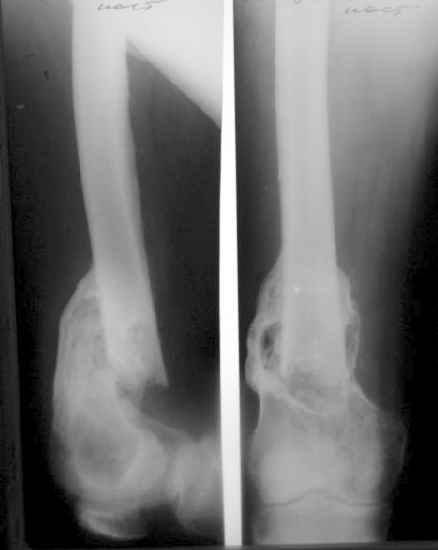

Пациент 53 лет травма 25.11.02. в салоне автомашины, получил множественные переломы ребер с ушибом легких и гемопневмотораксом, ротационно нестабильное повреждение таза: перелом боковых масс крестца, разрыв лонного сочленения, оскольчатый поперечный юкстатектальный перелом левой вертлужной впадины с центральным вывихом бедра и сегментарным переломом головки, перелом крыла правой подвздошной кости. Открытый многооскольчатый перелом костей правого предплечья, перелом правого бедра в нижней трети, перелом надколенника слева, перелом лодыжек левой голени с переломом заднего края левой большеберцовой кости подвывмхом стопы.Бедро срослось на вытяжении, лодыжки в гипсе, предплечье в аппарате. Под наше наблюдение попал 25.03.03. Выполнен чрескостный остеосинтез таза, с постепенной коррекцией положения отломков, затем 28.04.03 реконструкция вертлужной впадины для эндопротеза, синтез лонного сочленения. В настоящее время ходит с костылями, беспокоят боли в левом тазобедренном суставе, прогрессирует деформация головки. То есть в ближайших планах - эндопротезирование этого сустава. Однако смущает ряд моментов: В частности, на стороне предполагаемого эндопротезирования (левой) имеется разрыв собственной связки ниже надколенника, который подпаян к бедру (видно на фото сидя), то есть активного разгибания голени нет. А на правой стороне имеется штыкообразная деформация бедра, нет полного разгибания коленного сустава, хотя конечность опороспособна; ортопедическое укорочение 3 см.Вопросы: Что делать с левым надколенником и 4-главой мышцей? Восстанавливать ли ось и длину правого бедра? Если не трогать правое бедро, то на сколько компенсировать укорочение при эндопротезировании?

1. I would take down right femur nonunion and correct translation (it looks at very high risk to refracture), shortening and mild flexion deformity (these latter two corrections look like they would gain at least 1 cm of length.

I would not address the healed distal femor on the right. Leave it alone for now.